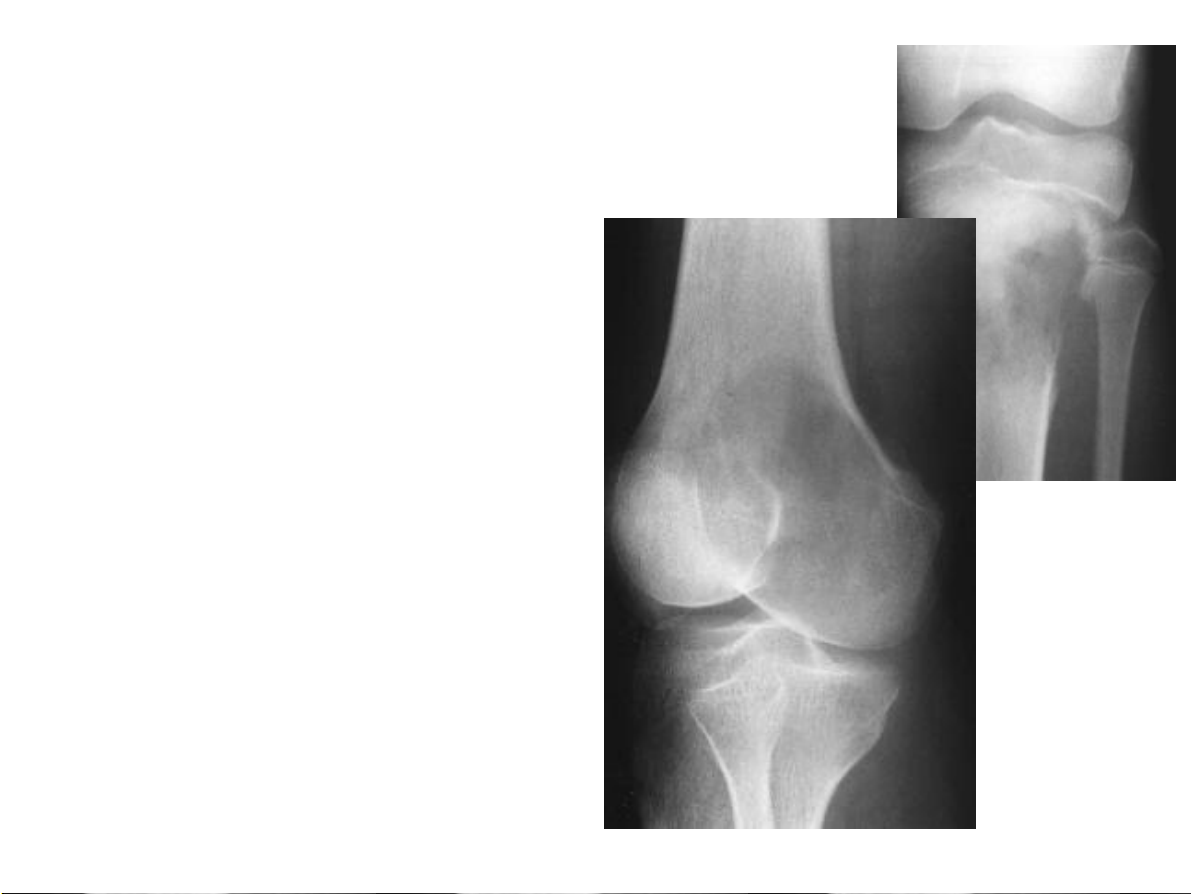

Bất thường về cấu trúc Tạo xương: phản ứng tân tạo xương 31-Jan-23 CĐHA Cơ-Xương-Khớp

Hai ví dụ của quá trình tân tạo xương. Phản ứng đặc xương ở chỏm

xương đùi và mái ổ cối trong thoái hóa khớp háng (hình A). Đặc xương

lan toả ở cột sống thắt lưng, xương cùng và xương chậu hai bên trong di

căn xương từ ung thư tiền liệt tuyến (hình B). 31-Jan-23 CĐHA Cơ-Xương-Khớp